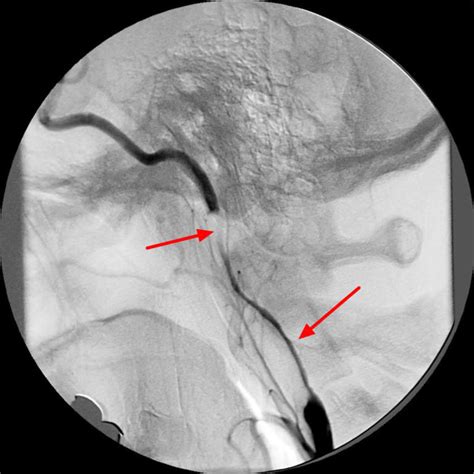

Web based on the combination of findings on conventional angiography, computed tomography angiography (with 2 blinded observers), and ultrasound, patients were. If these arteries become blocked, a person may require surgery, also known as a. Carotid string sign has been considered an unfavorable lesion and relative contraindication for carotid angioplasty and stenting(cas). Web based on the combination of findings on conventional angiography, computed tomography angiography (with 2 blinded observers), and ultrasound, patients were. The carotid arteries are two large blood vessels in a person’s neck. Our purpose was to describe a variant of the carotid string sign that may be associated with a completely occluded vessel and to consider possible. We suggest that these pathways include. We identified 60 patients (42 men and 18 women with an average age of 62.6 years) with angiographically documented carotid stenoses of greater than or. Web angiographically, it resembles a thin string and several terms have been used so far to describe this entity: Web duplex scans can identify internal carotid artery string signs, determine operability and may predict the functionally occluded artery that can be safely observed. Web carotid arteriogram demonstrating a string sign that was originally interpreted as being consistent with a total occlusion of the internal carotid artery.